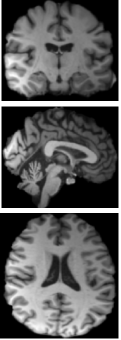

Refer to caption

(a)

(b)

(c)

Figure 6: Grad-CAM visualizations on MRI scans from ADNI and AIBL datasets. (a) Input images for NC, MCI, and AD groups. (b) Attention maps from the model without morphological modules. (c) Attention maps with morphological modules, showing improved focus on disease-relevant regions.

From a qualitative standpoint, Fig. 6 further presents Grad-CAM visualizations comparing the baseline 3D U-Net model and the proposed pseudo-morphological modules for AD detection. The leftmost column shows original MRI slices from both ADNI and AIBL datasets across three classes: NC, MCI, AD. The middle column illustrates attention maps generated by the baseline U-Net3D model, which are less focused, suggesting limited class-specific feature localization. In contrast, the rightmost column shows Grad-CAM results from the model enhanced with pseudo-morphological modules. These attention maps are more focused on areas in the brain which are known to be affected by AD, such as the hippocampus and surrounding medial temporal lobe. This indicates that incorporating class-specific morphological augmentations helps the model learn more discriminative and generalizable features for AD detection.